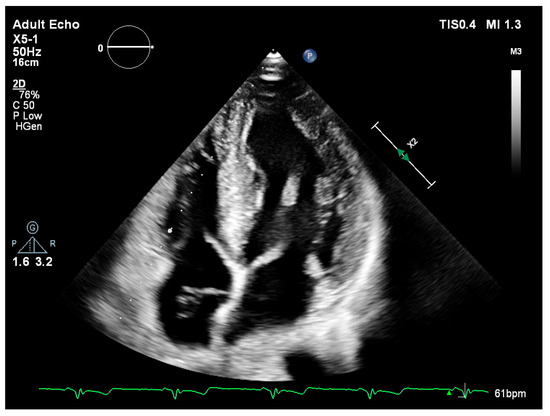

Left ventricular internal diameters in systole (LVIDs) and diastole (LVIDd) were slightly lower in FD patients compared to the non-FD group [LVIDs: 45.5 mm (36.0–49.0) vs. 47.0 mm (42.0–52.0); LVIDd: 28.0 mm (24.5–31.5) vs. 30.5 mm (25.3–37.0)] (Table 3). Measurements of wall thickness showed similar trends, with FD patients exhibiting slightly lower values in both posterior wall and interventricular septum thickness during systole and diastole. Notably, the median interventricular septum thickness in diastole (IVSd) was 15.5 mm (IQR: 15.0–16.0) in FD patients compared to 18.0 mm (IQR: 16.0–22.5) in the non-FD group (Table 3). Left ventricular ejection fraction (EF) was preserved in both groups, with a higher median value observed in FD patients [65.0% (65.0–65.0) vs. 60.0% (55.0–65.0)]. Right ventricular function as measured by TAPSE was also slightly higher in FD patients [25.0 mm (25.0–30.0)] versus non-FD patients [23.0 mm (20.0–28.0)] (Table 3). There were no marked differences in left atrial and right atrial dimensions or filling pressures between groups. The E/A ratio and E/E′ values in FD patients were within the expected range and comparable to non-FD patients (Table 3). Figure 1 (parasternal long-axis) and Figure 2 (apical four-chamber) present concentric left ventricular hypertrophy consistent with hypertrophic cardiomyopathy in a patient with genetically confirmed Fabry disease (own clinical material).

Figure 2. Transthoracic echocardiography—apical four-chamber (A4C) view showing concentric left ventricular hypertrophy.